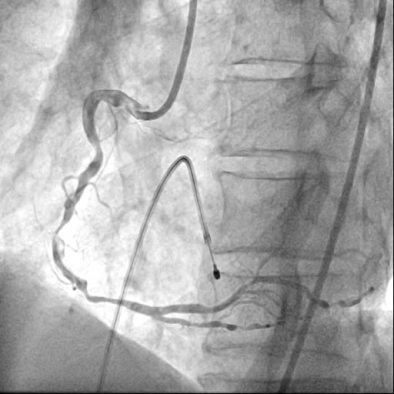

급성 하벽 ST분절 상승 심근경색에 합병된 완전방실차단으로 진단하고, 신속하게 일시적 심박동기를 우심실에 삽입하여 박동수를 회 복시킨 뒤에 관상동맥 조영술을 하였다. 우관상동맥의 심한 협착과 혈전으로 인한 급성 폐색을 확인하고 (그림 2, 동영상 1), 풍선카테 터와 스텐트를 이용한 일차적 관상동맥중재술을 통해 재관류치료를 하였다 (그림 3, 동영상 2).